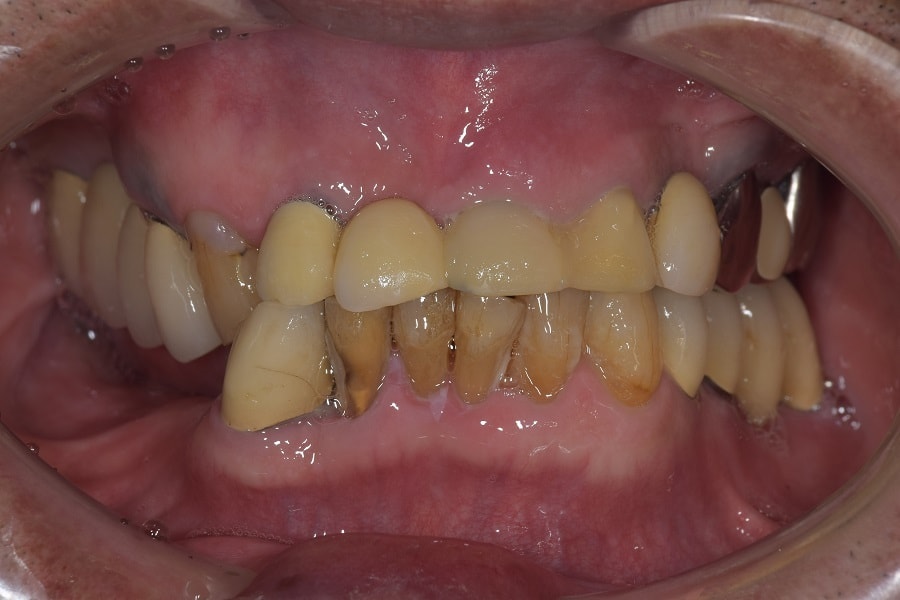

咬むと前歯が痛いと来院された患者さん。奥歯がないため、前歯に負担がかかり、下の歯がないまま放置していたため、上の歯が下に下がってしまうなど様々な問題をお口の中に抱えていました。

治療前のかみ合わせのままで治療しても長持ちしないこと、本来のかみ合わせから崩れてしまっていると判断し、お口の中を総合的に治療する治療方法を提案させていただき治療を行いました。

残すことが出来ない歯の抜歯などを行うと、すれ違い咬合という治療するには難しいかみ合わせであったことなど、仮の入れ歯などで咬合状態の経過観察などを行ったため治療期間は約2年ほどかかりました。